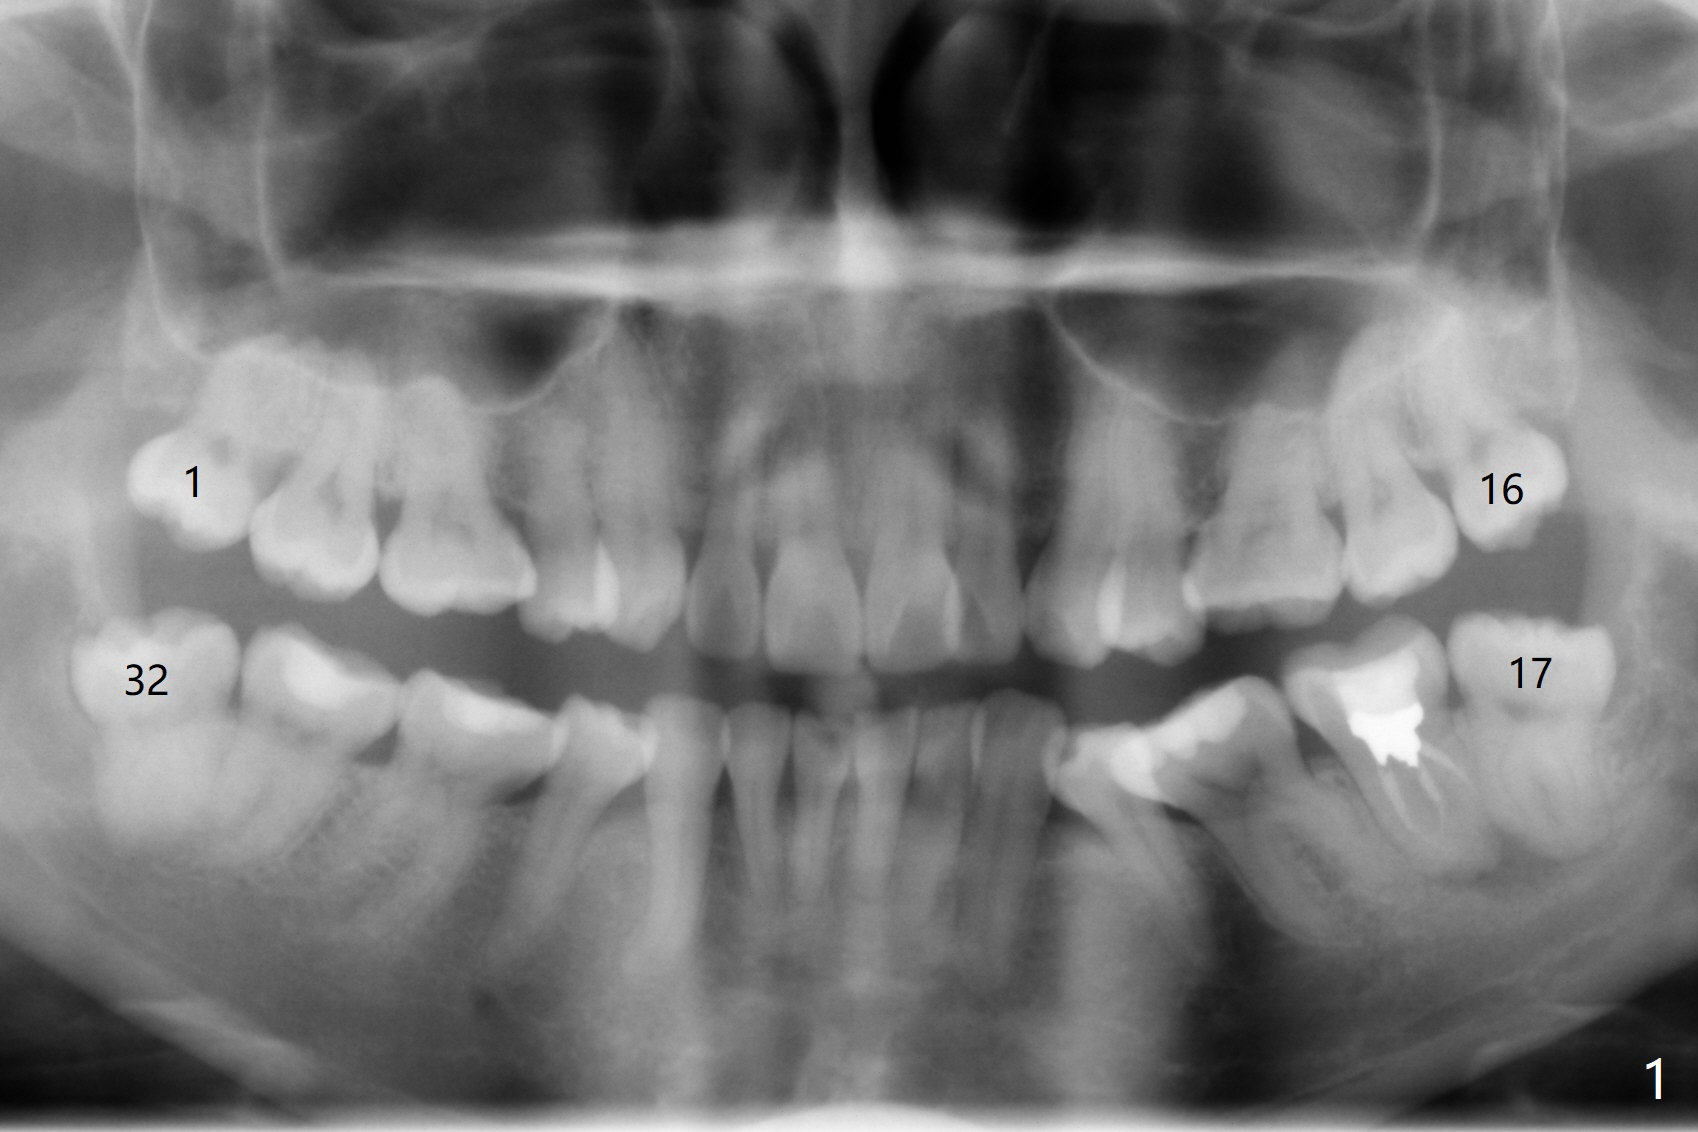

RCT Retreat, Apical Surgery Before 3rd Molar Bone Graft

A 37-year-old woman requests extraction of the 3rd molars and orthodontic retreatment (Fig.1). Since the bone between #17 and 18 is thin and short (Fig.2 black *), bone graft is needed after #17 extraction. But the apical infection at #18 (Fig.2 white *) may affect graft survival. The patient agrees to have RCT retreatment done (Fig.3 white curved lines) before extraction (black area). The apical granulation tissue can be removed (Fig.4 red area) prior to bone graft (Augma). The latter will be also placed at #17 as a control. After endodontic consultation, the patient does not want RCT retreatment. She would like to have the 3rd molars extracted first and #18 removed if needed. After #17 extraction (Fig.5), apicoectomy will be performed at #18 (Fig.6 (white outline: surgical bur, use non-torque handpiece)). Following curettage of the apical lesion at #18 (Fig.7), bone graft will be placed (Fig.8 red circles). In fact the patient insists upon #1, 16, 17, and 32 extraction. After extraction, allograft (Fig.9 A (Ossogen, Mineralized Cort/Can (30%/70%), .25-1.0 mm) is placed in the mesioapical of the sockets of #17 and 32, while Osteogen Plug (O) and BioXclude in the distocoronal one (4-0 PGA suture). There is minimal bone between the 2nd and 3rd molars (black arrowheads). The allograft is intentionally pushed into #18 apical defect after enucleation (white arrowhead). The sockets are slightly open, although sutures are in place 2 weeks postop (Fig.10,11). It is unknown whether the bone graft is partially dislodged or not.